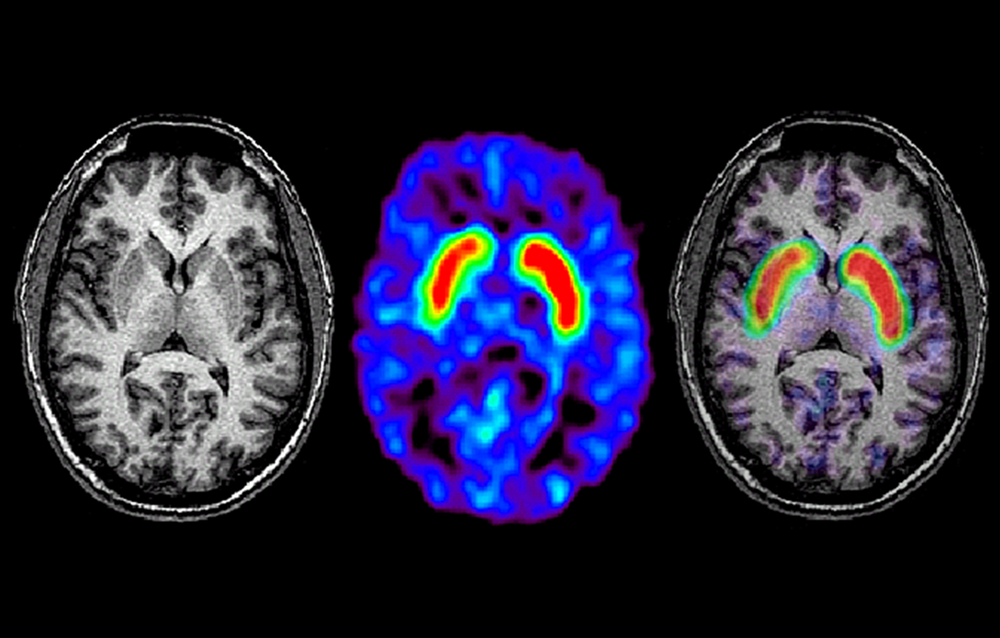

MRI may be used to identify Parkinson disease biomarkers that can inform diagnosis, track disease progression, and elucidate the neurobiological underpinnings of symptoms.

“With MRI, we are now looking at the brain structurally, functionally, and metabolically, and we are seeing advances in evaluating the brain as related to various symptoms and correlating those with different structural changes,” Ritesh A. Ramdhani, MD, assistant professor of neurology and neurosurgery at New York University Langone Health’s Fresco Institute for Parkinson’s & Movement Disorders, told Neurology Advisor. MRI may be used to identify PD biomarkers that can inform diagnosis, track disease progression, and elucidate the neurobiological underpinnings of symptoms.3

Qualitative changes in the substantia nigra (SN) can be detected by iron- and neuromelanin-sensitive (NS) MRI, and quantitative markers can be revealed via diffusion-weighted imaging, MR volumetry, and iron-sensitive imaging. Alterations in functional connectivity can be identified with functional MRI, and researchers are exploring “which connectivity changes are unique to the Parkinson’s brain compared to the normal brain, and whether these changes are related to patient symptomatology or if they are a precursor of what’s to come,” Dr Ramdhani told Neurology Advisor